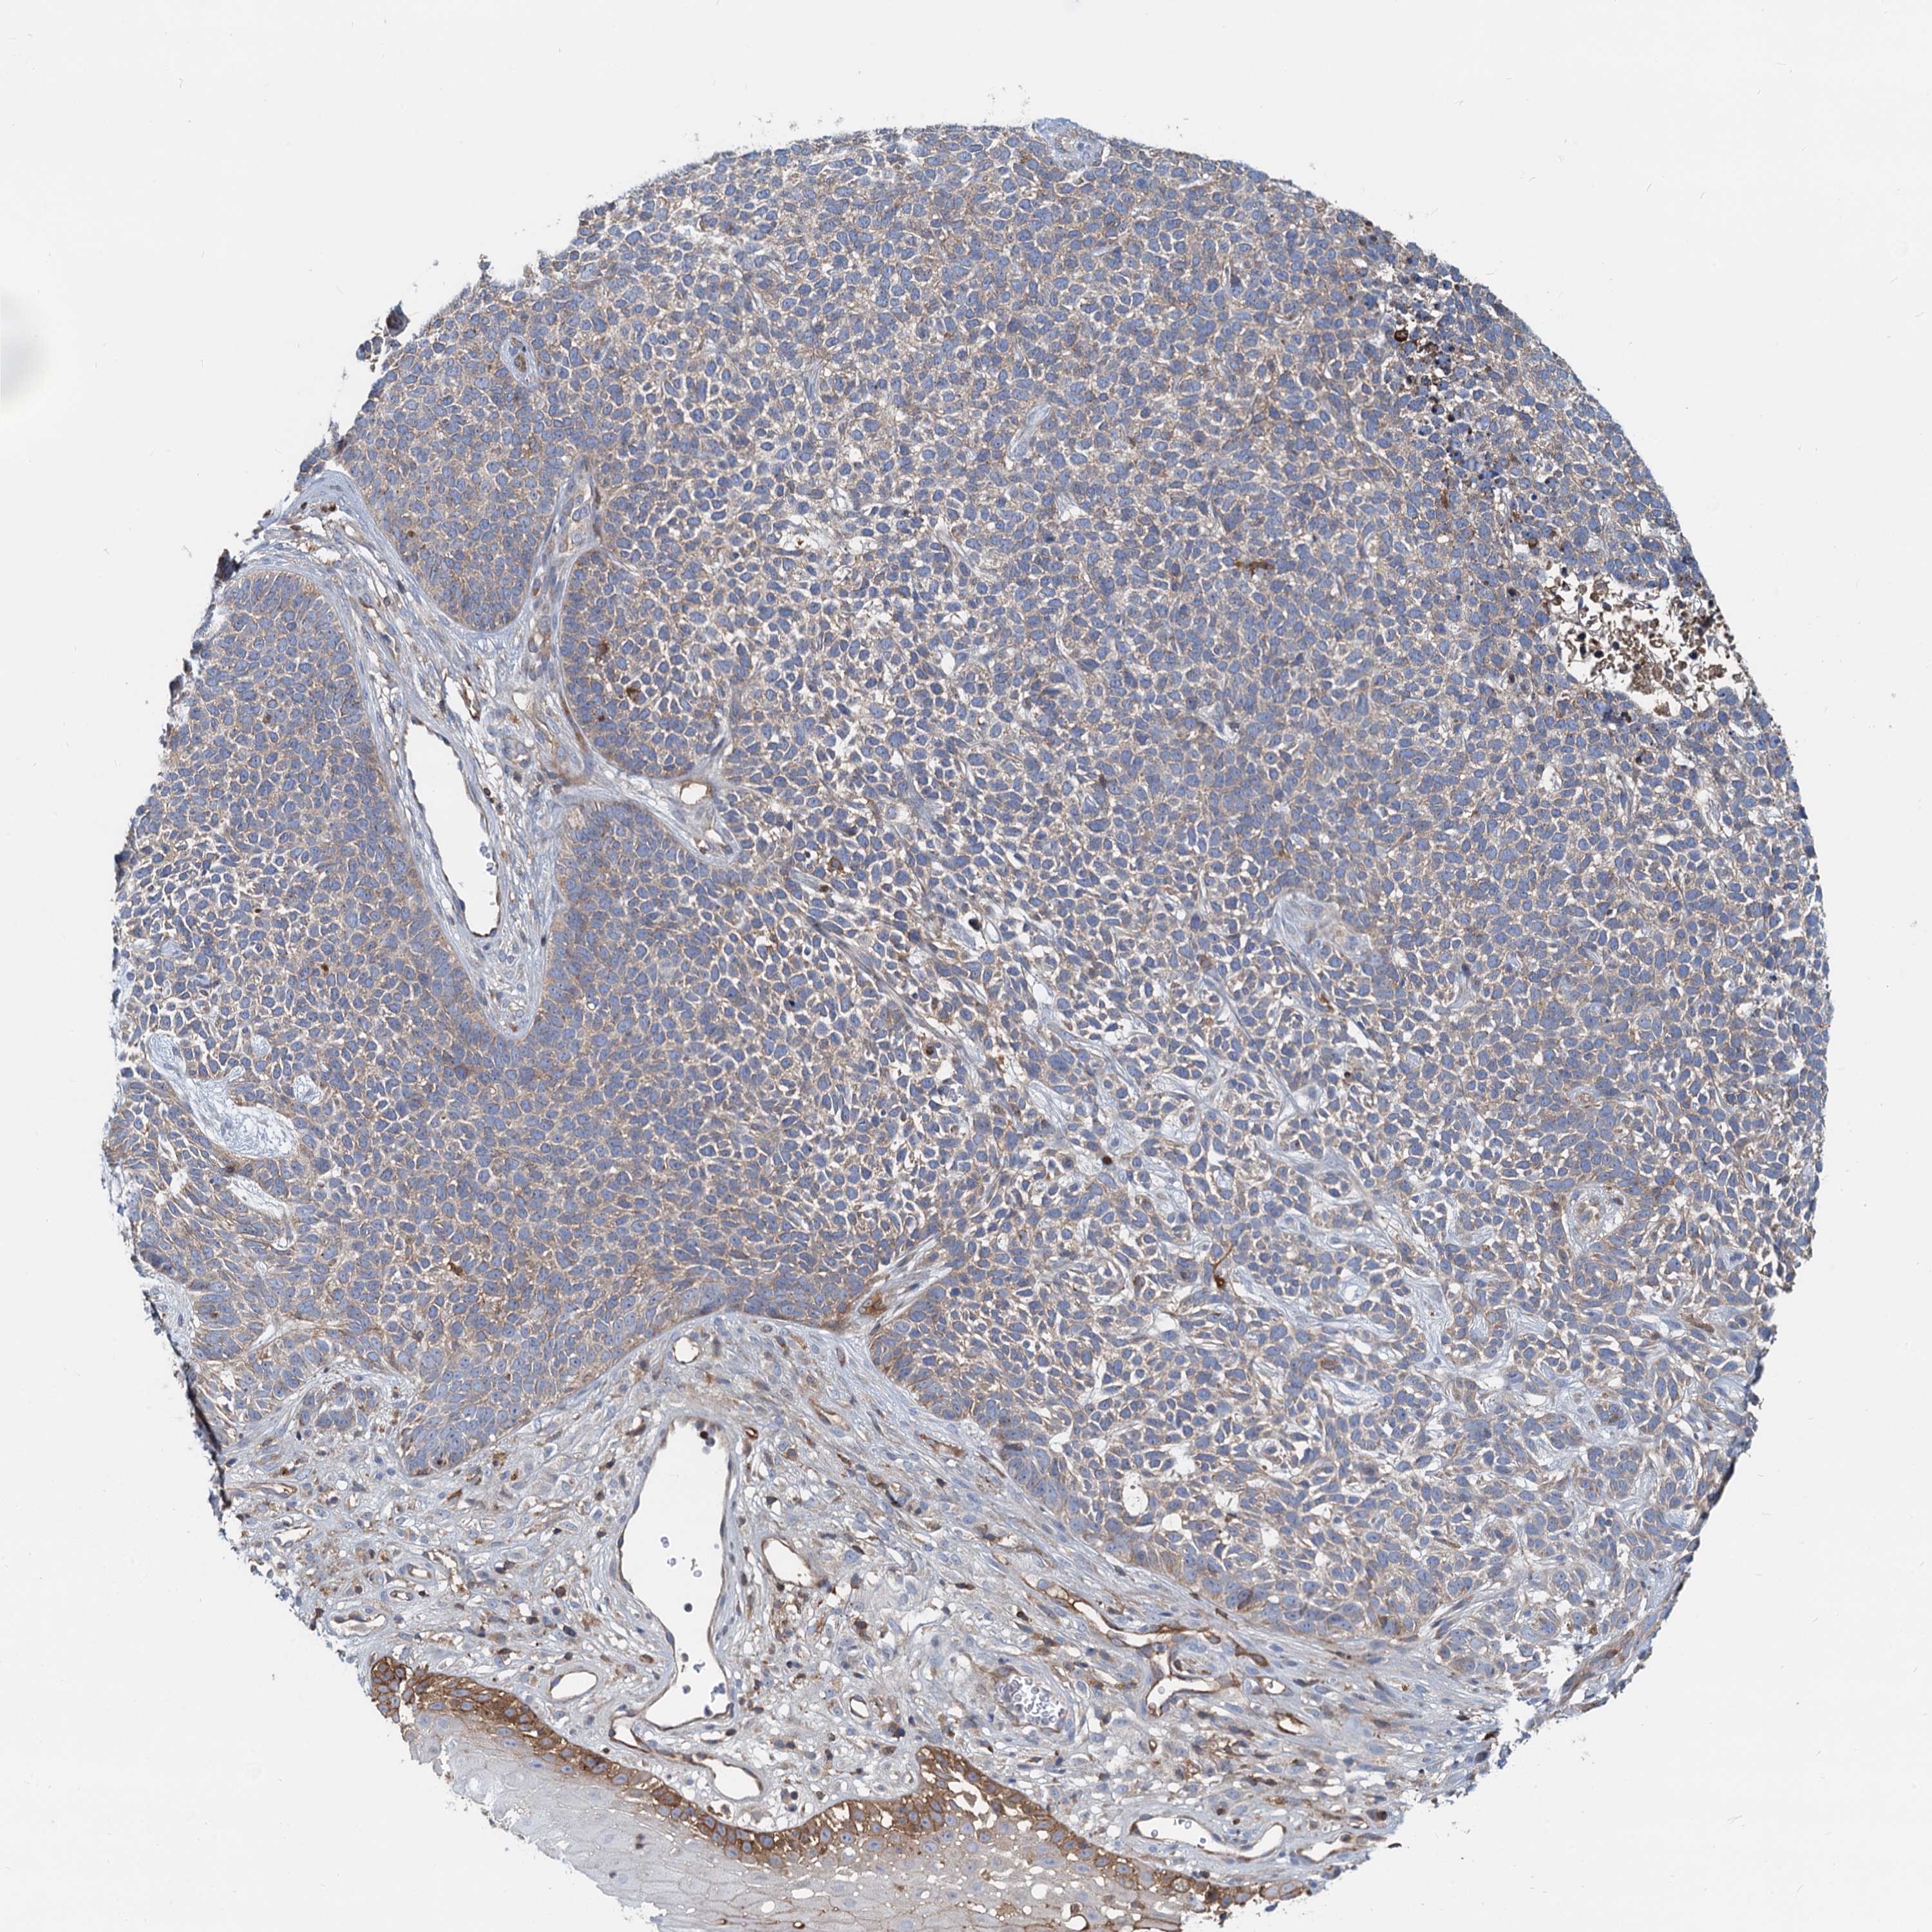

SKIN CANCER - Protein expressioni

A mouse-over function shows sample information and annotation data. Click on an image to view it in a full screen mode. Samples can be filtered based on level of antibody staining by selecting one or several of the following categories: high, medium, low and not detected. The assay and annotation is described here.

Antibody staining in the annotated cell types in the current human tissue is reported as not detected, low, medium, or high, based on conventional immunohistochemistry profiling in selected tissues. This score is based on the combination of the staining intensity and fraction of stained cells.

Each image is clickable and will lead to virtual microscopy that enables deeper exploration of all samples and also displays staining intensity scores, fraction scores and subcellular localization as well as patient and tissue information for each sample.

Antibody HPA040698

Basal cell carcinoma